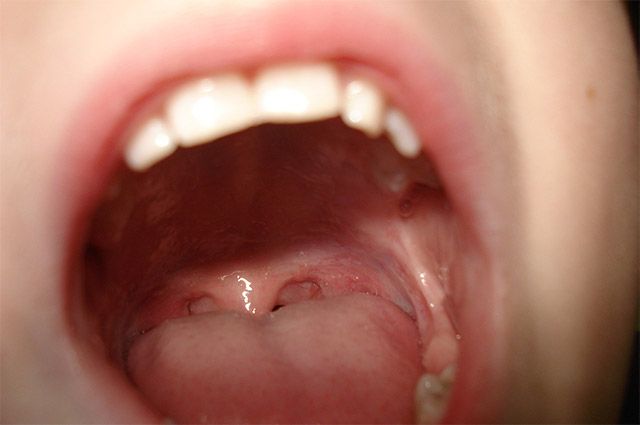

구강암은 입천장부터 잇몸, 볼 점막, 혀, 혀 밑바닥, 어금니 뒷부분, 턱뼈 혹은 입술, 구인두(혀의 후방부), 목과 연결되는 부위 등 입 안 어디서든 발생할 수 있다. 특히, 혀와 상악 및 하악을 포함한 잇몸, 볼 점막 등에서 가장 많이 발생한다.

구강 내 백색을 띠는 백반증이나 붉은 반점, 구내염과 같은 염증성 궤양이 3주 이상 지속되는 경우, 혹은 병변의 범위가 넓거나 출혈, 통증이 지속된다면 조직 검사 등의 정밀 검사를 받아야 한다.